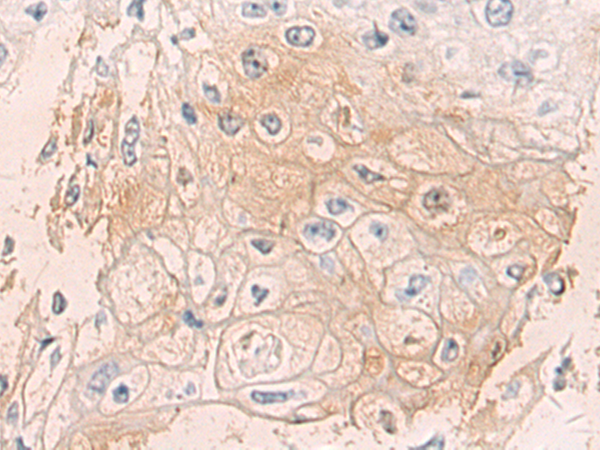

IHC positive control: |

Human esophagus cancer |

IHC Recommend dilution: |

50-100 |